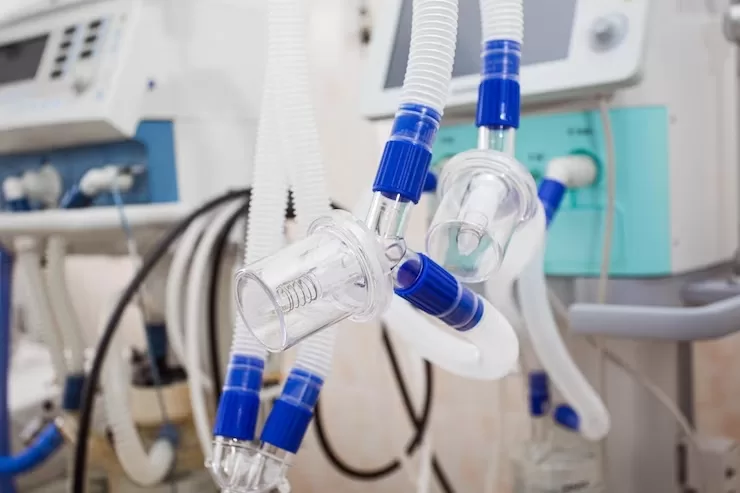

1. Teknologi Pulmotor/Alat Pernapasan Buatan

Pulmotor adalah alat yang digunakan untuk melakukan proses pernapasan buatan. Alat ini biasanya digunakan pada pasien atau orang yang mengalami gangguan pernapasan, seperti gangguan pernapasan karena tenggelam dan kaget saat tersengat listrik.

Bentuk Pulmotor yang digunakan dalam keadaan darurat dan yang berbeda di rumah sakit berbeda. Pulmotor yang ada di rumah sakit dilengkapi dengan tabung oksigen berukuran besar, dan biasanya dilengkapi dengan instalasi khusus yang memudahkan untuk proses penggunaannya.

Pulmotor yang dilengkapi tabung oksigen lebih cepat membantu proses pemulihan pernapasan, karena setelah penyimbatan ditarik keluar, maka oksigen langsung dimasukkan ke tubuh pasien, sehingga diharapkan kondisi pasien bisa segera pulih seperti sediakala.